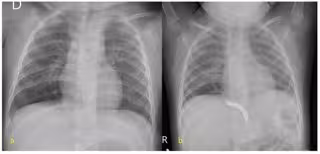

El protocolo de seguimiento establecido incluye una radiografía de control a las 24 horas de la intervención y sucesivas seriadas cada seis meses.

En concreto, el diagnóstico de la paciente, que se realizó de forma prenatal, era un secuestro pulmonar intralobar en lóbulo inferior derecho con una rama aferente procedente de la aorta abdominal de cuatro milímetros de calibre y un drenaje venjoso a las venas pulmonares, confirmado mediante radiografías y angioTC, que había presentado varios procesos infecciosos.